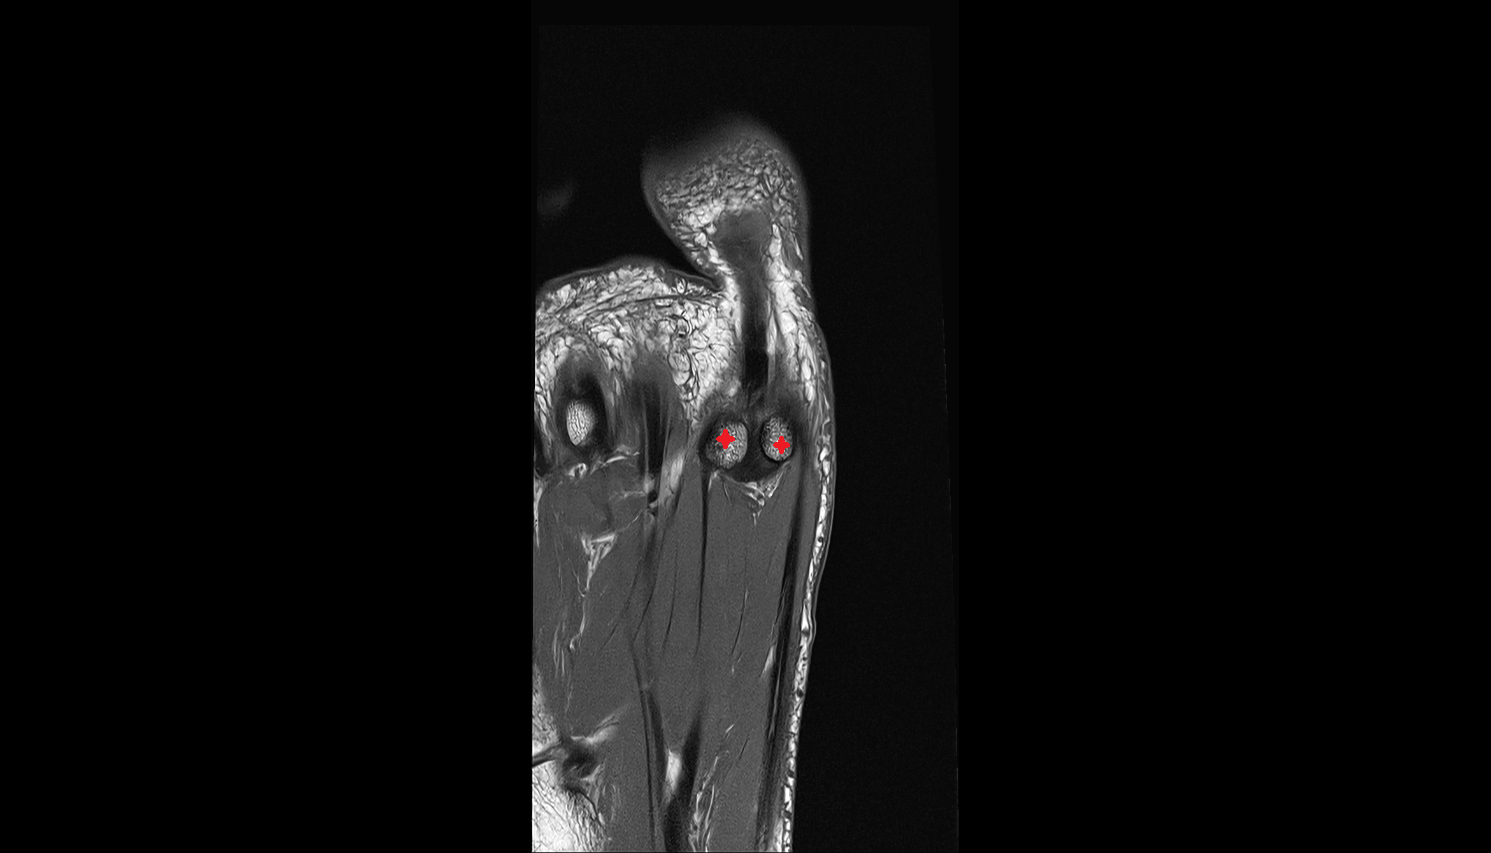

- Sesamoid bone of great toe

- Lateral sesamoid bone

- Medial sesamoid bone